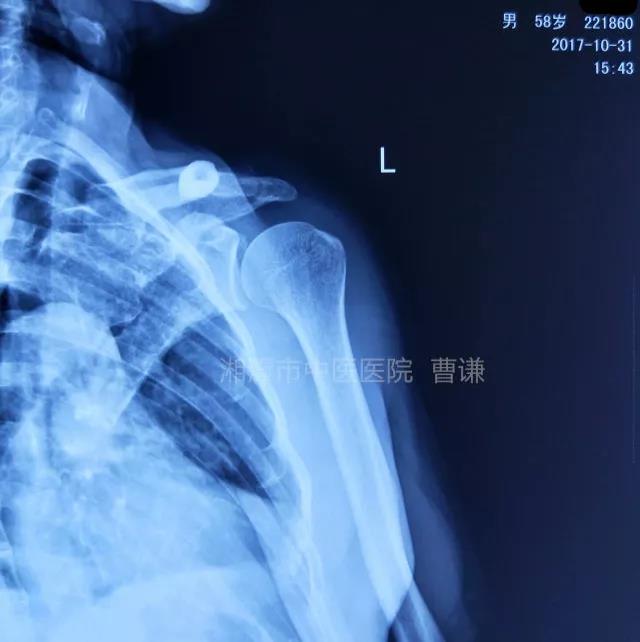

简要病史:骑摩托车跌倒致左肩部肿痛,活动受限,就诊于当地医院,拍片及磁共振检查后诊断为肩袖损伤及肩关节半脱位,予以悬吊固定,因症状缓解不明显就诊于我院。外院拍片情况如下:

应该说是一个典型的“灯泡征”影像,但是并未引起注意。